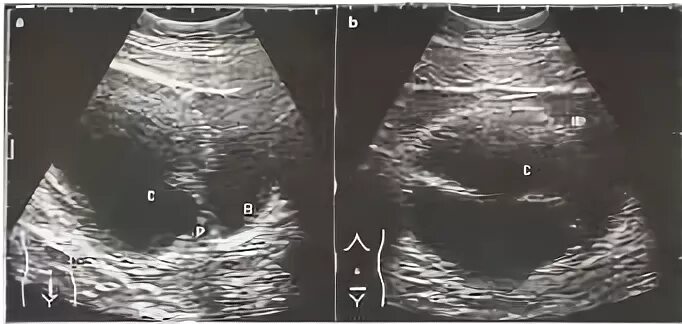

Перекрут придатков матки